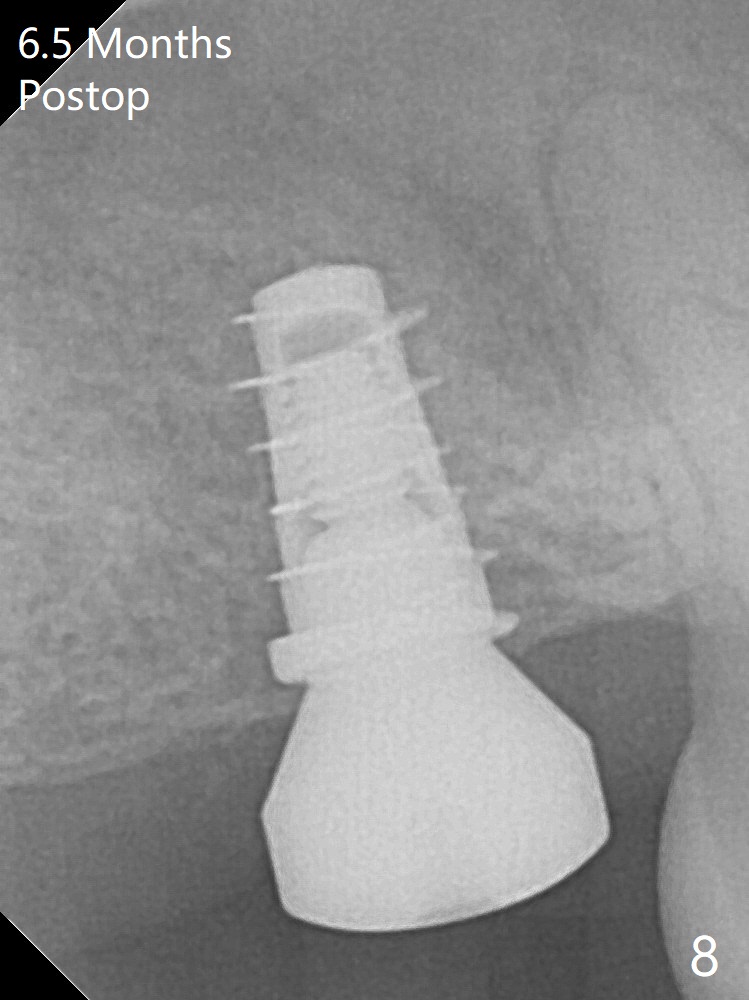

With 4-5 mm remaining bone at #2, the initial osteotomy is 4.0x3.5 mm with regular drills with sharp end. After using 3.6 mm sinus drill with round end for ~ 4 mm in depth, water lifting is conducted smoothly. After use of the same safe drill for ~ 5 mm, water lifting is done. Nose blowing indicates possible sinus membrane perforation. With insertion of collagen plug (PRF is not prepared because of thin vein), mixture of autogenous bone and allograft is lifted with 4x9 mm dummy implant with a guide (Fig.1 G). With placement of more of bone graft, a 4.5x7 mm definitive implant is placed with ~ 25 Ncm (Fig.2). Although bone graft around the implant is limited (Fig.3,4 *), the sinus membrane is lifted (in fact expanded by water) substantially (arrowheads, as compared to preop CT). The healing abutment is dislodged 1 month postop. Before impression, use sensor 1 to take PA to determine whether the abutment contacts the crestal bone or not. Take 5x5 cm CT for sinus membrane thickness. Although the bone graft surrounds the implant 3 months postop, the implant is tender when a 4.5x4(2) mm cemented abutment is being placed (Fig.5). Later a healing screw is placed (Fig.6,7). The sinus membrane has shrunk (arrowheads). Progressive loading is mandatory. The implant is uncovered with a 6x2 mm healing abutment 6.5 months postop (Fig.8). A 5.5x4(2) mm pair abutment is placed and torqued at ~20 Ncm with mild tenderness 7 months postop (Fig.9 BW). A provisional is fabricated for progressive loading because of mild crestal bone loss (*). The abutment is able to be torqued at 35 Ncm 9 months postop. Impression is taken. Return to Upper Molar Immediate Implant Trajectory II 18 Next Case with 3-4 mm Bone Screw Xin Wei, DDS, PhD, MS 1st edition 10/29/2019, last revision 02/23/2021